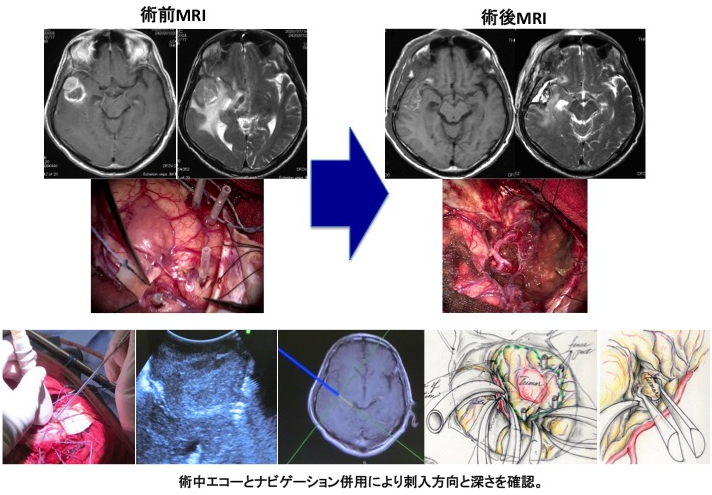

腫瘍の位置情報(解剖学的情報)、どこに重要な脳の働きをする場所があるかの情報(機能的情報)、摘出したものが腫瘍であるかどうかの情報(組織学的情報)を参考に、腫瘍を最大限に摘出することが可能になりました。一見すると判別しにくい腫瘍と正常脳の境界を迷うことなく同定するには、術中ナビゲーションは不可欠です。

また、言語や運動機能に関与している領域に近いところに存在している腫瘍を摘出する際には、運動誘発電位を施行し、術後に半身不随(麻痺)を防ぐべく摘出操作を進めております。正常組織とグリオーマ組織の境界は肉眼的に不明瞭であるため、術者の見極めが困難であるため、どこまで摘出すべきかを確認するためには、腫瘍境界部の組織を摘出し、前述した5-ALAによる光線力学的診断と手術中に迅速病理診断を併せて行っております。これらは、次世代を担う若手術者の育成ツールとしても極めて有用です。